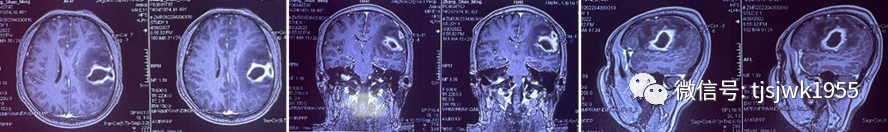

4月30日,48岁王先生(化名)因间断头痛已有一周时间,想是偏头痛,慢慢会恢复。但突然发现,右侧肢体偏瘫,且言语表述不清,这才被家人从外地紧急送往同济医院神经外科,磁共振检查后,发现左侧颞顶叶巨大囊性占位,囊壁强化明显,考虑脑脓肿。

考虑到病灶主要位于功能区,神经外科舒凯教授仔细阅片后,立即为患者个体化制定了手术机器人辅助下精准穿刺脓肿引流减压的治疗策略。在手术机器人的实时导航下,以微小切口钻孔后,引流管被精准送入脓肿中心,引流出黄绿色脓液10余毫升,手术在30分钟内完成,全程基本无血操作。术后患者清醒,头痛明显缓解,右侧肢体肌力恢复至2级。